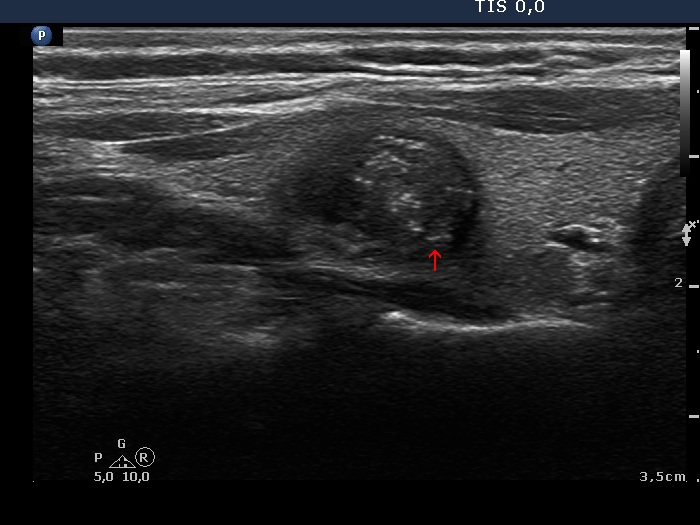

Papillary carcinoma (histological diagnosis) |

This case is less edifying or may be more edifying. Compared with the previous case, the granules here are less bright. Nevertheless, great proportion of them belong to punctate echogenic foci (arrows). It is worth to compare these with non-specific granules (arrowheads). |